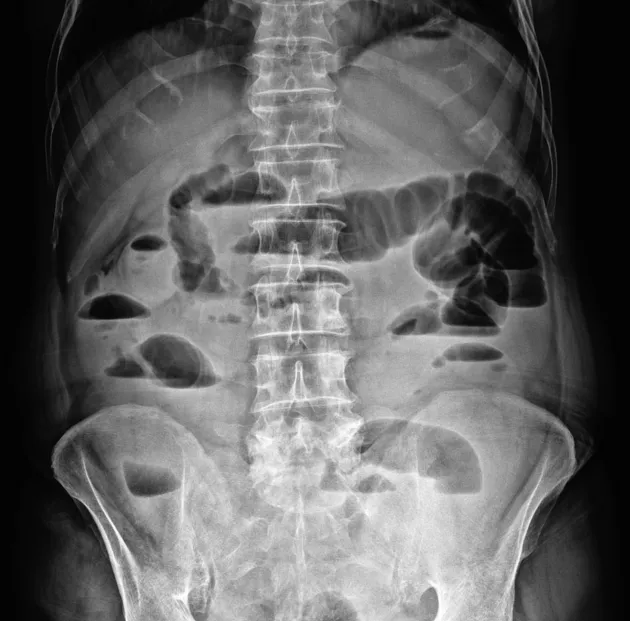

- Abdominal X-ray (AXR): Initial imaging.

- Dilated small bowel loops (>3 cm).

- Multiple air-fluid levels on upright film.

- Paucity of gas in the colon.

- Abdominal X-ray shows dilated small bowel loops (>'''3 cm''') with air-fluid levels.